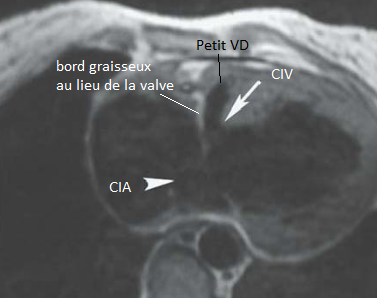

Atresie de la Valve tricuspide

- Bord graisseux et musculaire en lieu et place de la valve tricuspide

- VD hypoplasique

- CIV et CIA